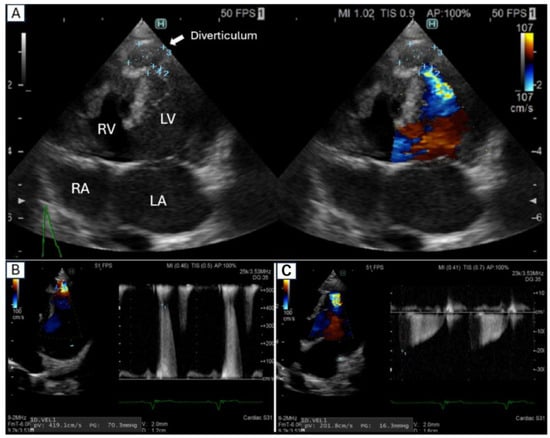

3. Echocardiography